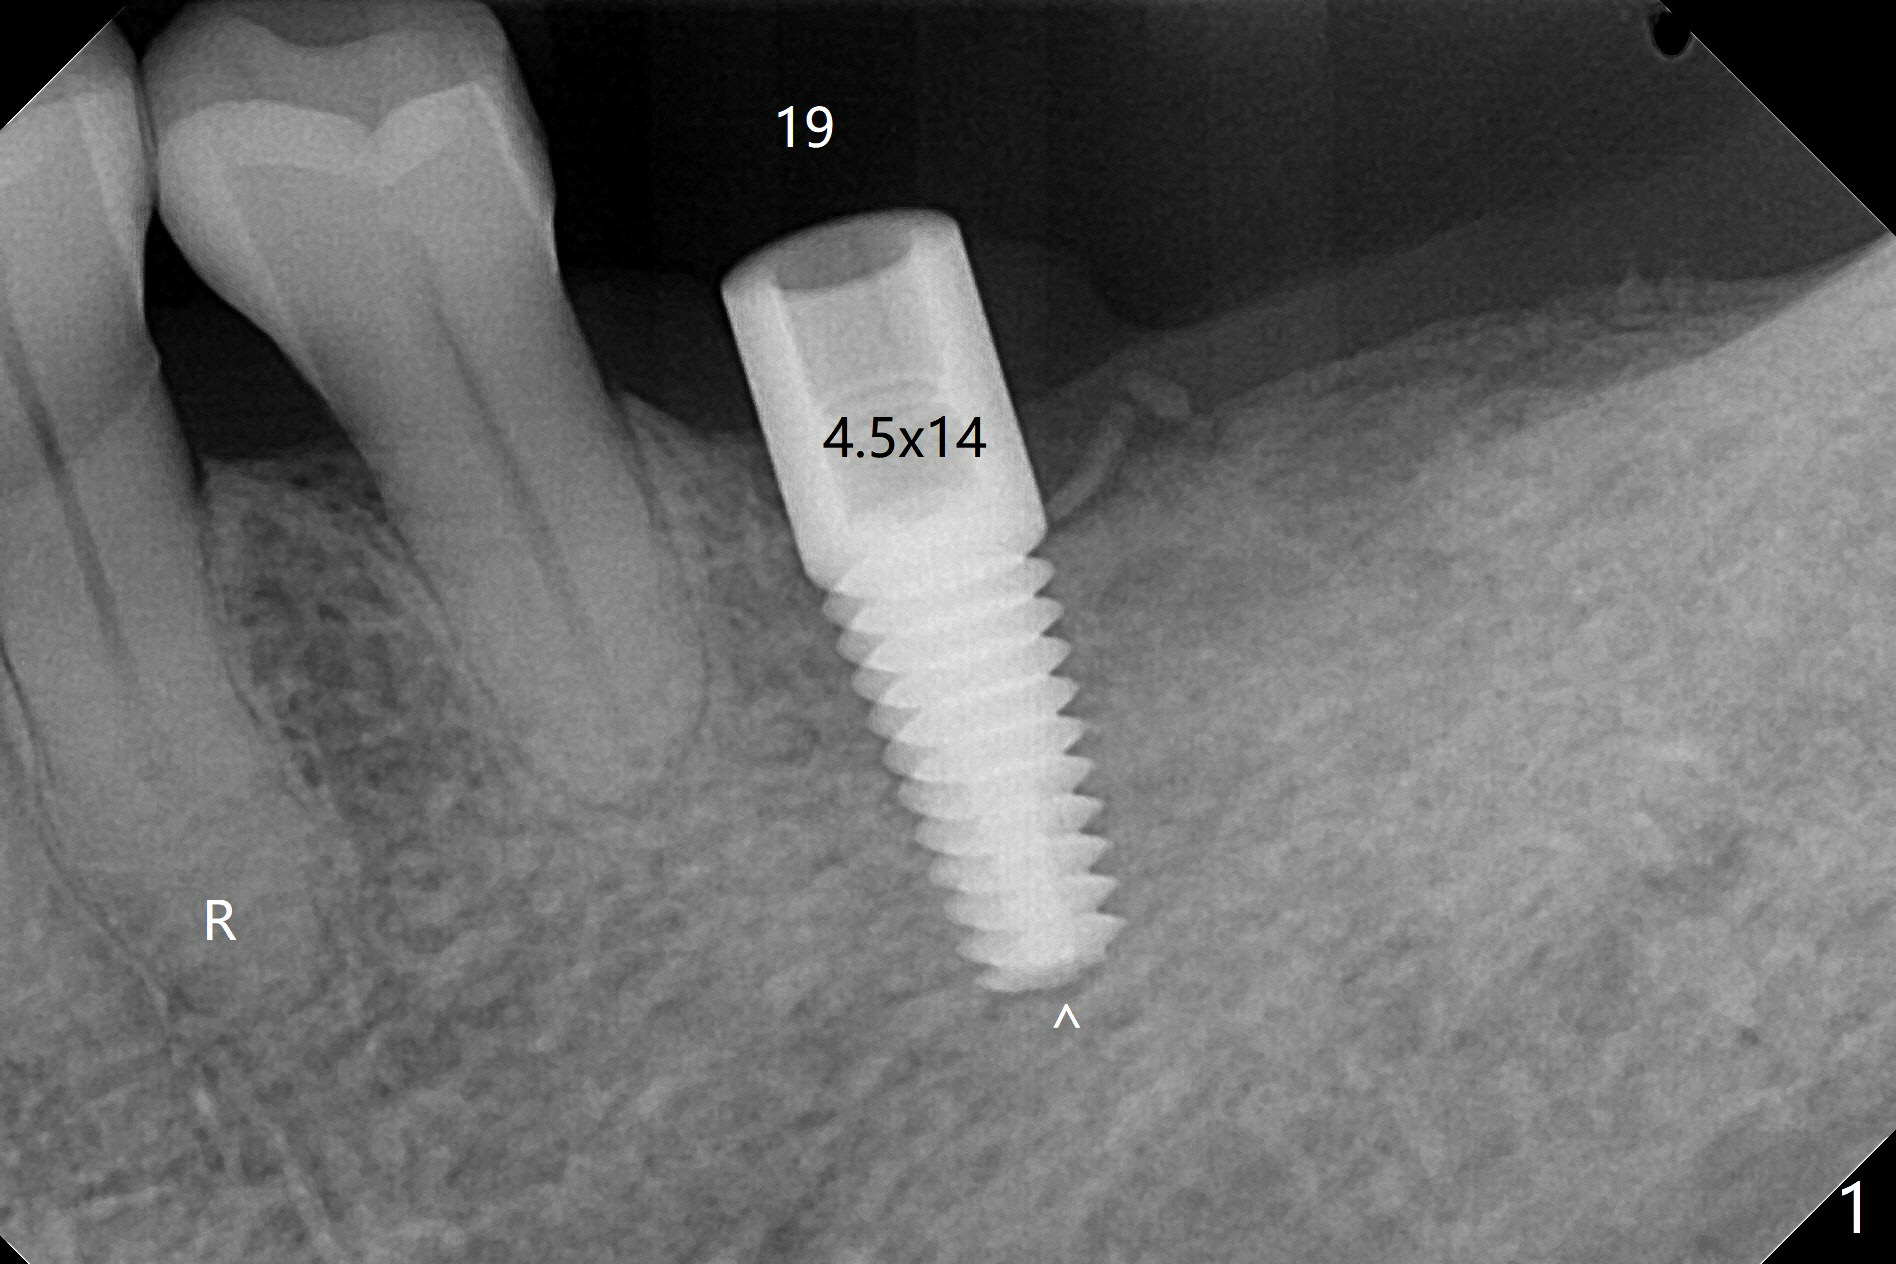

Following light use of 4 mm tissue punch, a buccal incision is made and raised. After 4x8.5 mm drill with 10.5 mm offset at #19, 4.5 mm cortical drill is used for 2/3 length to take care of the thick dense lingual plate (overprep). The remaining apical 3 mm osteotomy is underdrill (3.5 mm). After try-in of a 4.5x14 mm tissue-level dummy implant, a same-sized definitive one obtains 35 Ncm torque (Fig.1). Following 3-4 more turns, the torque reaches 45 Ncm (Fig.2) with the distal thread covered (<) and autogenous bone graft placed in the distal defect (*). A 4x3 mm unipost is placed to keep periodontal dressing in place. Clinically the implant is placed within bone boundary buccolingually. The new implant seems necessary considering short (Fig.2 S) and probably resorbed (Fig.1 R) roots of the premolars. In fact the short abutment keeps the mesiolingual portion of periodontal dressing for 2 weeks; since local hygiene is suboptimal, the healing screw is placed after abutment and dressing removal (Fig.3).